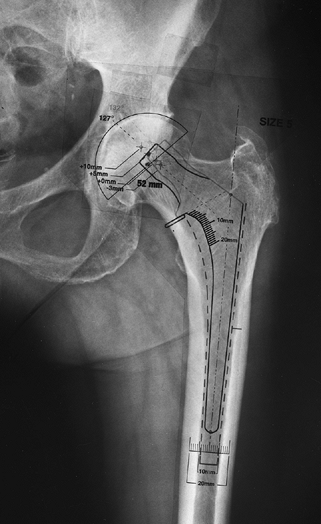

acetabular polyethylene (126). Choose a prosthesis that restores femoral offset (Fig. 105.9).

If an implant of proper size cannot restore offset, then consider a

stem design with a higher femoral offset. Many implant companies now

provide implants with high and standard offset options. High offset

stems commonly provide better restoration of femoral offset without

excessive leg lengthening in patients with

varus

femoral necks. Restoring femoral offset allows the abductors to

function more efficiently (thereby reducing limp) and also helps

restore soft-tissue tension (thus improving hip stability).

![]() |

Figure 105.9.

The femoral offset is the horizontal distance from a line drawn through the center of the femoral canal along its long axis to the center of the femoral head. AP hip radiographs taken with the hip externally rotated tend to underestimate the true femoral offset. |

design, and size on leg length and femoral offset. Once the center of

hip rotation is determined by acetabular templating, the difference

between the femoral head center and the acetabular center on templating

predicts change in leg length: if the templated center of the femoral

head is superior to the templated acetabular center, the leg will be

lengthened by that amount, and if the templated center of the femoral

head is inferior to the templated acetabular center, the leg will be

shortened by that amount (Fig. 105.10). The

position of the templated femoral head center to the templated

acetabular center from medial to lateral corresponds roughly to femoral

offset restoration (Fig. 105.10).

Figure 105.10.

AP hip radiograph with acetabular and femoral templates demonstrating the position of possible modular femoral neck lengths relative to the planned center of hip rotation (The inferior dot marks the center of the acetabular component.) Femoral head centers inferior to the planned center of the acetabulum shorten the leg relative to the preoperative condition, whereas femoral head centers superior to the planned center of the acetabulum lengthen the leg relative to the preoperative condition. Likewise, femoral head centers lateral to the planned center of the acetabulum reduce femoral offset relative to the preoperative status, whereas femoral head centers medial to the planned center of the acetabulum increase femoral offset relative to the preoperative status. The term femoral offset in this context is used as an approximation because true femoral offset refers only to the femur and is not dependent on the center of the acetabulum. The patient’s symptomatic leg was 4 mm shorter than the opposite side preoperatively so the femoral component position is chosen to provide proper leg length reconstitution with a +5 mm modular neck length. To obtain proper femoral offset, and thus to help restore soft tissue tension and abductor lever arm, a high-offset femoral component is chosen. |